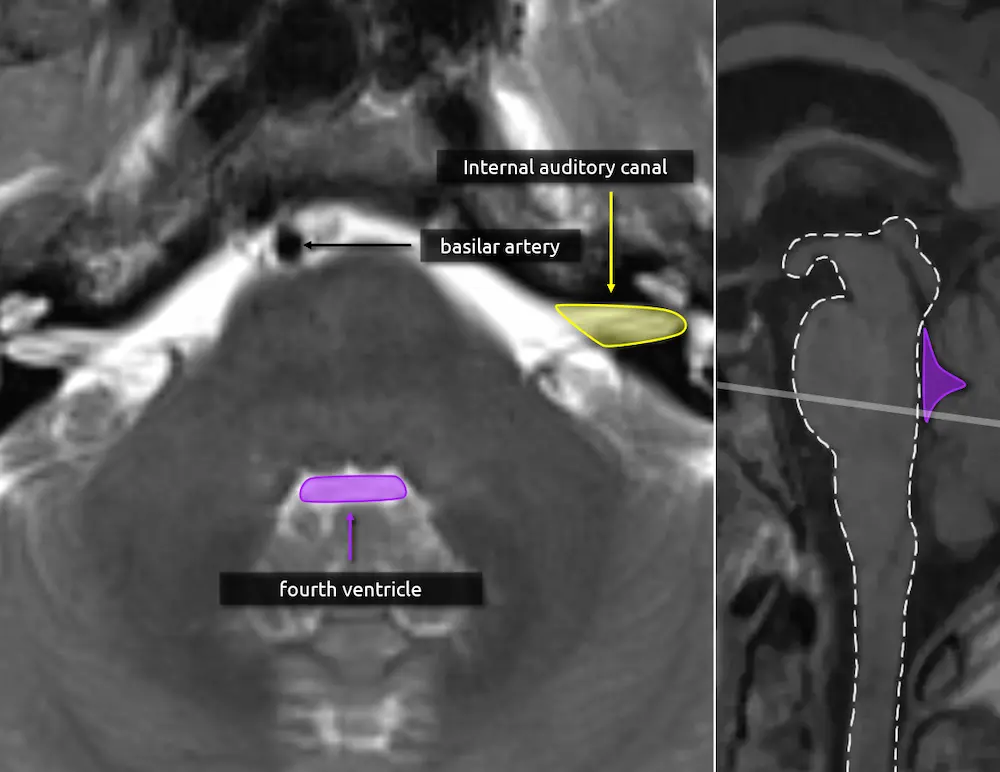

1. Fourth ventricle

2. Basilar artery

3. Internal auditory canal

The internal auditory canals (IACs) are useful landmarks to identify the caudal (lower) part of the pons and thus several important nuclei that will be introduced in later levels.